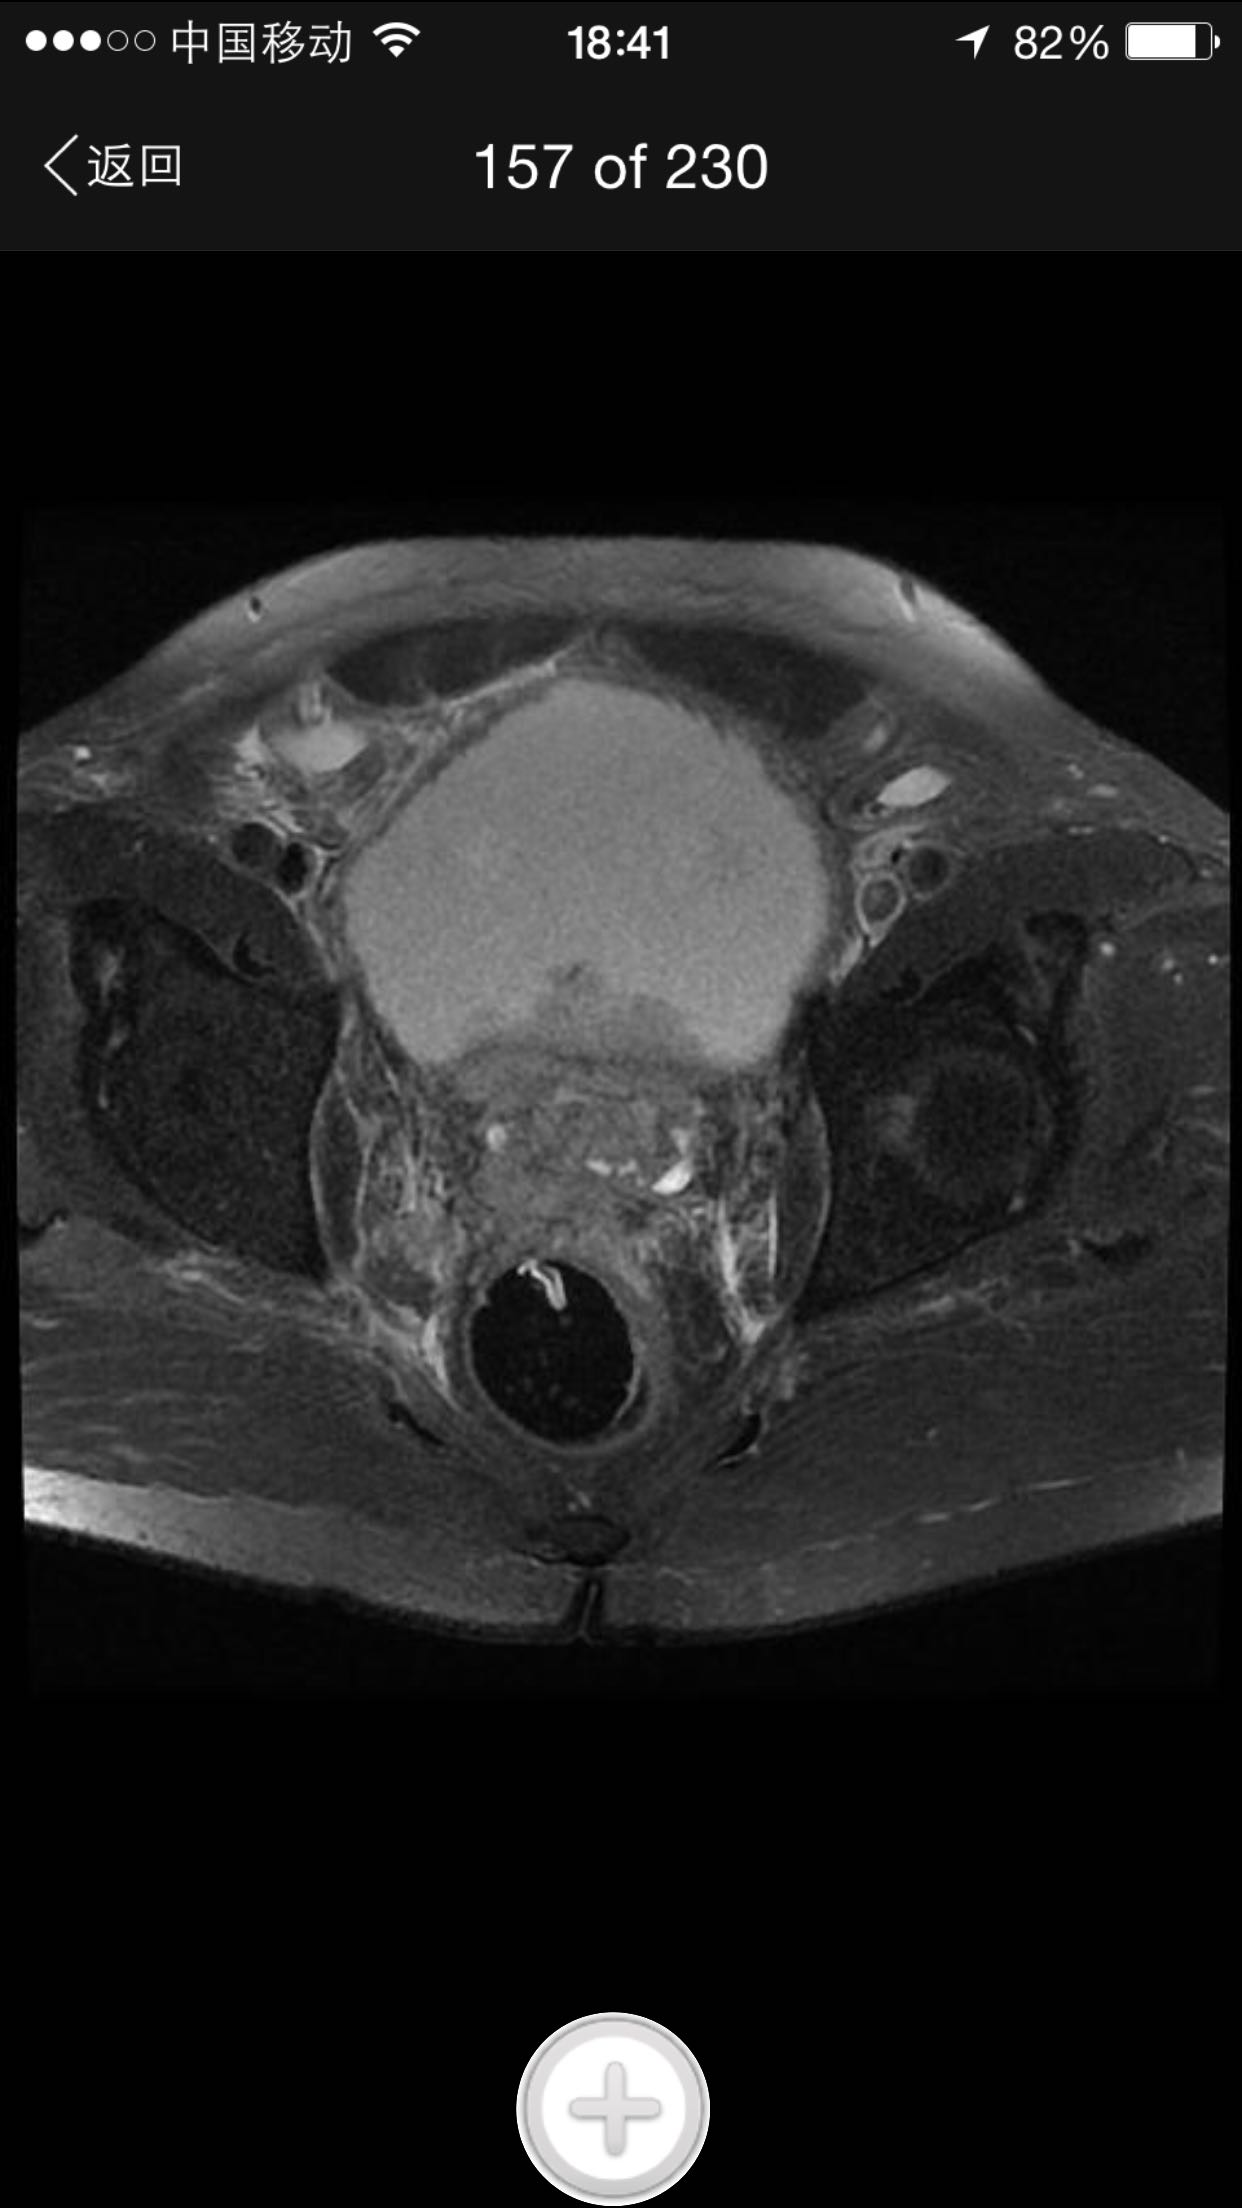

肛诊:前列腺增大,质硬,可扪及多个硬结。 PSA329ng/ml。

诊断:前列腺癌晚期 尿潴留 治疗:考虑患者临床分期较晚,T4期,且淋巴结转移,合并尿潴留,超声提示肾积水,决定行TURP,解决排尿困难。术中快速,如为前列腺癌,直接行手术去势。术中按上述方案处理。术后病理为前列腺中分化腺癌。